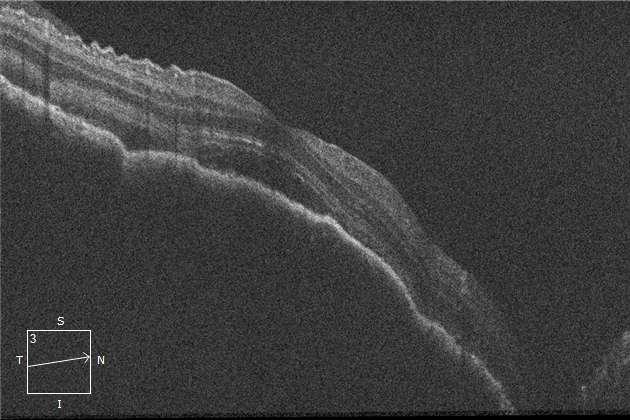

2. HIDROPS CORNEAL

Caso aportado por Dr. Matías Ramirez y Dra. María José Vergara

Bü También conocida como hidropesía aguda, ocurre por una rotura de la membrana de Descemet, permitiendo la entrada aguda y súbita de humor acuoso en el espesor corneal, provocando edema. A

ü Se presenta de forma aguda con dolor disminución de la agudeza visual y fotofobia.

ü Paciente de 9 años con antecedentes de síndrome de down consulta en unidad de trauma ocular por disminución de la agudeza visual.

ü Al examen físico se evidencia en ojo derecho (imágenes A, B, C y D):

ü Hiperemia conjuntival

ü Edema corneal marcado con engrosamiento estromal, presencia de bullas estromales y subepiteliales asociado a opacidades lineales verticales.

ü Protrusión y deformidad cónica central con adelgazamiento corneal sobre borde paplpebral

ü Hendidura en forma de V en parpado inferior (signo de munson).

ü Tras la resolución del edema corneal queda una cicatrización estromal de grado variable.